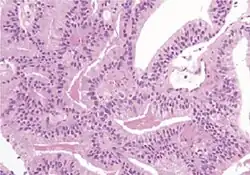

Pseudohyperplastic carcinoma 2%[5] 11%[5]

• Large-sized or dilated glands[1]

• Branching and papillary infolding[1]

• Tall columnar cells[1]

• Abundant pale to slight granular luminal cytoplasm[1]

• Nuclei towards basement membrane[1]

Tumorous glands:

• 34βE12- and p63- [1]

• AMACR+ in 70–83% of cases[1]

3+3=6[1]